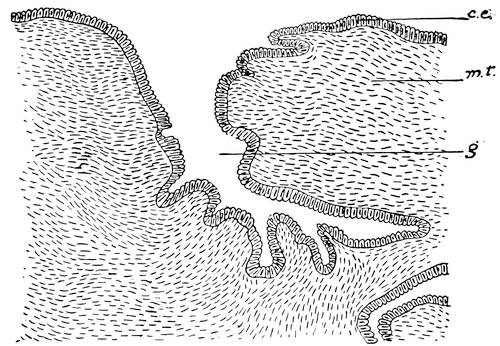

Mons of Venus, labia majora, minora, vestibule, bulbs, clitoris, Bartholinian glands, hymen, vagina, uterus, broad and round ligaments, viiitubes, ovaries, Graafian follicle, ovum.

Function of ovaries, ovum, Graafian follicle, tubes, menstruation, function of uterus, female ejaculation, function of vagina, Bartholinian glands, of clitoris, course of the sexual act.

At this period a little semicircular crescentic fold attached to the dorsal margin of the aperture of the vagina arises and forms the hymen, an organ which has always played such an important rôle in the fancy of all nations.